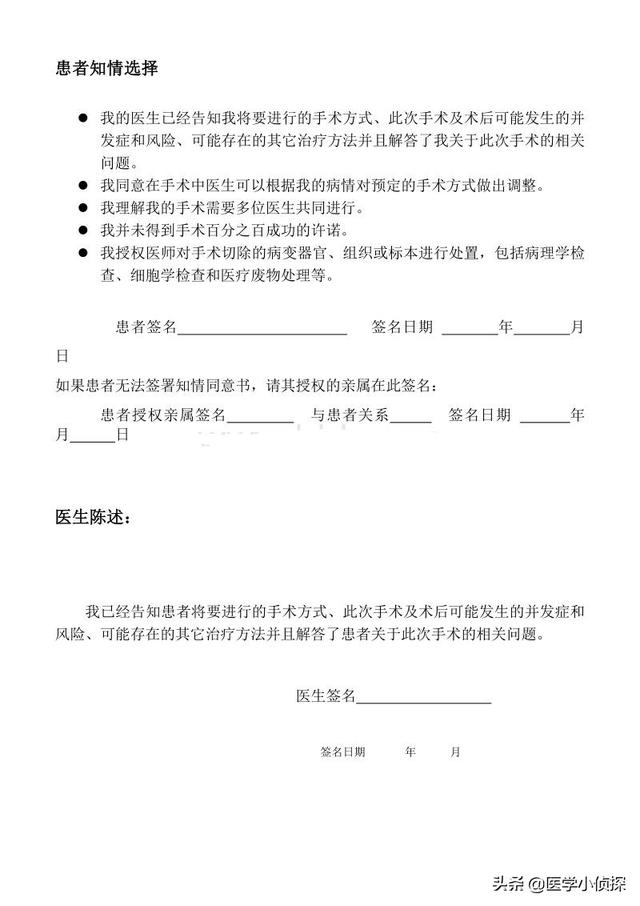

手術や医療行為には必ずリスクが伴います。心臓ステントが心臓の中で手術されるものであることは言うまでもありません。 リスクや合併症があるのは普通のことで、手術を受ける前に患者さんやご家族がよく理解しておくべきことです。

そして私たち医師は各患者の手術前には、患者やその家族とコミュニケーションをとり、事前にあらゆる合併症や起こりうるリスクを明記したインフォームド・コンセント用紙に署名する。第一に、造影剤にアレルギーを起こす人もいれば、穿刺点に合併症を起こす人もいれば、心臓や血管経路全体に合併症を起こす人もいる。例えば、造影剤にアレルギーのある人もいれば、穿刺点に合併症のある人もいれば、心臓や血管経路全体に合併症のある人もいるなど、どのような合併症でも他の多くの問題を引き起こす可能性がある。

しかし、この合併症がすべての患者に必ず起こるというわけではないし、リスクがあるからといって手術を受けないということでもない!また、重篤な合併症と軽度の合併症がある。 造影剤を1回注射しただけで重篤なアレルギー反応を起こす人もいれば、何も起こらないか、特に軽い症状の人もいるが、これはやはり個人の体質や体調が関係している。冠動脈造影が原因で死亡するケースは年間約2万~3万件ありますし、冠動脈疾患に対する心臓ステント留置術は、私たちだけでも1つの病院で毎年数千件行っています。ですから、冠動脈造影は比較的安全で、基本的にはステント治療を受けても問題ありません。